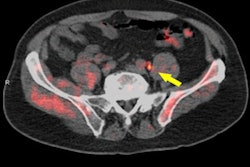

After validating the utility of PKM2 as a PET reporter gene in cell culture studies, the researchers tested their system on mice that were infected with the adeno-associated virus (AAV). They imaged the mice with small-animal SPECT/CT of F-18 DASA-23 over a period of two months to track the increase in PKM2 gene expression over time. Confirmed by F-18 DASA-23 uptake studies and mRNA analysis, the results showed good correlation (r2 = 0.69, p < 0.05) between PKM2 and the radiotracer, according to the researchers. What's more, additional analysis showed a significant increase in PKM2 expression in infected mice compared with controls.

(A) Representative contrast-enhanced T2-weighted MR coronal image of AAV-transduced mouse brain. (B) Corresponding merged F-18 DASA-23 PET/MR images (10 to 30 minutes summed F-18 DASA-23 activity). The white arrow indicates regions of radiotracer uptake corresponding to the transduced region. (C) Autoradiography of mouse brain sections excised one hour after radiotracer administration and (D) an immunofluorescence stain for PKM2. Image courtesy of Thomas Haywood, PhD, et al and Stanford University School of Medicine.PKM2 has the potential to be further developed into a PET reporter gene system for the imaging of gene therapy in the CNS, the researchers concluded. In addition to testing in mice, the radiotracer has also recently been used at Stanford in the first human trials for the early detection of a therapeutic response in glioblastoma.